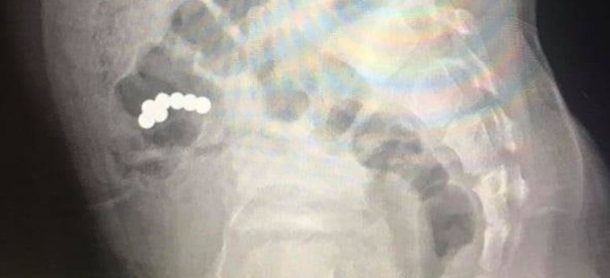

На Прикарпатье прооперировали проглотившего семь магнитов ребенка (фото)

В Ивано-Франковске медики прооперировали пятилетнего мальчика, который проглотил семь магнитных шариков из игрушки. Обошлось без осложнений, передает FaceNews.ua.

Во время рентгенологического исследования диагностировали наличие магнитов в кишечнике. Предметы не продвигались в течение 10 дней. Это стало показанием к оперативному хирургическому вмешательству.

Во время операции хирурги обнаружили сращение стенки тонкой кишки, где находились четыре магнита, со стенкой слепой кишки, где были три магнита. Медики удалили лишние предметы.